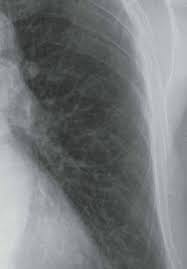

The decrease in other more severe symptoms is wheezing which if. Sarcoidosis is often identified as swollen hilar lymph nodes found in chest radiography during routine physical checkups. Sarcoidosis is a somewhat common pulmonary disease, but the concurrence of lung cancer and sarcoidosis in the same patient is very rare. Read about sarcoidosis, a chronic lung disease. By magdalena kegel | august 12, 2016.

Read about sarcoidosis, a chronic lung disease. Board certification in internal medicine. Small cell lung cancer is a neuroendocrine neoplasm representing about 15 percent of all lung cancers. Managing sarcoidosis involves monitoring your symptoms closely to track the effectiveness of treatments. Sarcoidosis is an inflammatory disease that affects one or more organs but most commonly affects the lungs and lymph glands.

Sarcoidosis is a chronic inflammatory condition that may increase the risk of cancer, but limited information is available on occurrence of cancer in results were generally consistent among ethnic groups, although the increased risk of colon and kidney cancer was observed only in white patients. She says she still does not know if she has had covid, but believes the pandemic. Managing sarcoidosis involves monitoring your symptoms closely to track the effectiveness of treatments. Board certification in internal medicine. The disease is referred to as systemic lesions. Read about sarcoidosis, a chronic lung disease. Sarcoidosis is a multisystem granulomatous disorder of unknown etiology that affects individuals worldwide and is characterized pathologically by the presence of noncaseating granulomas in involved organs. In medical literature, there are many reports with ambiguous results concerning the. Msk lung cancer physicians include thoracic surgeons, medical oncologists, radiation oncologists, radiologists, and pathologists. Because sarcoidosis can escape diagnosis or be mistaken for several other diseases, we can only guess at how many people are affected. Sarcoidosis is often identified as swollen hilar lymph nodes found in chest radiography during routine physical checkups. Sarcoidosis most often affects the lungs and may cause lung problems, such as: Sarcoidosis is currently thought to be associated with an abnormal immune response.